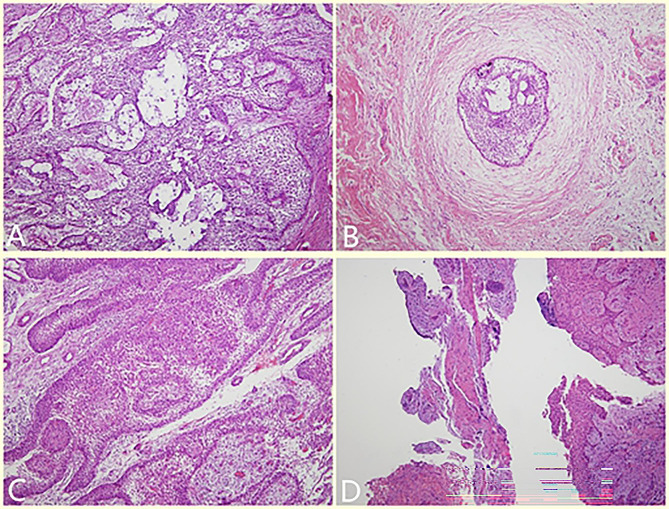

Fig. 2.

Histopathological photos (HE staining,100X). A, Tumor cells arranged in a follicular or plexiform pattern with abundant cells, evidenced by the active proliferation of interstitial fibrous tissue. B, Pathology after treatment showed obvious degeneration, with only partially odontogenic epithelium seen. C, Tumor cells arranged in a follicular or plexiform pattern, revealing the appearance of classic AM. D, Pathology after treatment showed hyperplastic fibers and mucosal epithelium, and a small amount of reticular hyperplasia of the squamous epithelium was observed focally

After the operation, the patient wore the plug device, and the outpatient examination was carried out regularly (Fig. 4). At 10 months after the second operation (April, 2020), the patient was readmitted to the hospital for surgery to close the window. During the procedure, if the fenestration remained and the bottom was shallow, an incision was designed along the perimeter of the fenestration. The mucoperiosteum of the fenestration was excised, the bone surface was exposed, and the soft tissue in the bone cavity was removed. Combined with the medical history, the local lesions were consistent with AM, with fibrous tissue tumor-like hyperplasia and hyaline degeneration. The mucoperiosteum was released on both sides of the window, and the adjacent flap was turned to close the window. The postoperative paraffin-embedded section showed a fibrous capsule wall-like tissue, lined with stratified squamous epithelium, which had odontogenic features (Fig. 2B). Combined with the medical history, the local lesions were consistent with AM. The patient was followed up for 15 months after the window was closed. No recurrence was found. Osteogenic remodeling could be seen in the bone cavity. The shape of the original bulging jaw returned to normal (Fig. 5).

Classic AM is easy to relapse when only curettage is used in the treatment because AM has a certain degree of bone infiltration and multilocularity. Unlike the cyst wall with complete boundaries, it is difficult to eradicate all tumor cells by curettage. Residual tumor cells are easy to recur. However, the following two goals will be achieved if decompression is performed simultaneously. ① Changing the environment in which tumor cells survive. The osteoclast-promoting cytokines secreted by the epithelial cells of the cyst wall are released into the oral environment. The changes in the microenvironment of the cyst cavity cause changes in the tumor epithelium. Different pathological changes, such as keratinization and hyalinization, appear, and the tumor epithelium gradually degenerate, eventually, transforms into the oral mucosa epithelium [29]. This point was also confirmed by the pathological changes of the two patients in this study (show in Fig. 2). ② Reducing the pressure of tumor invasion into bone tissue and rebalancing osteoclast and bone remodeling. Under the dynamic effect of mandibular growth and reconstruction, the rate of osteogenesis is much greater compared with tumor osteoclasts (especially in children). When a new balance is achieved (the jaw bone lesions are no longer reduced), two-stage surgical curettage can be used to obliterate the tumor.